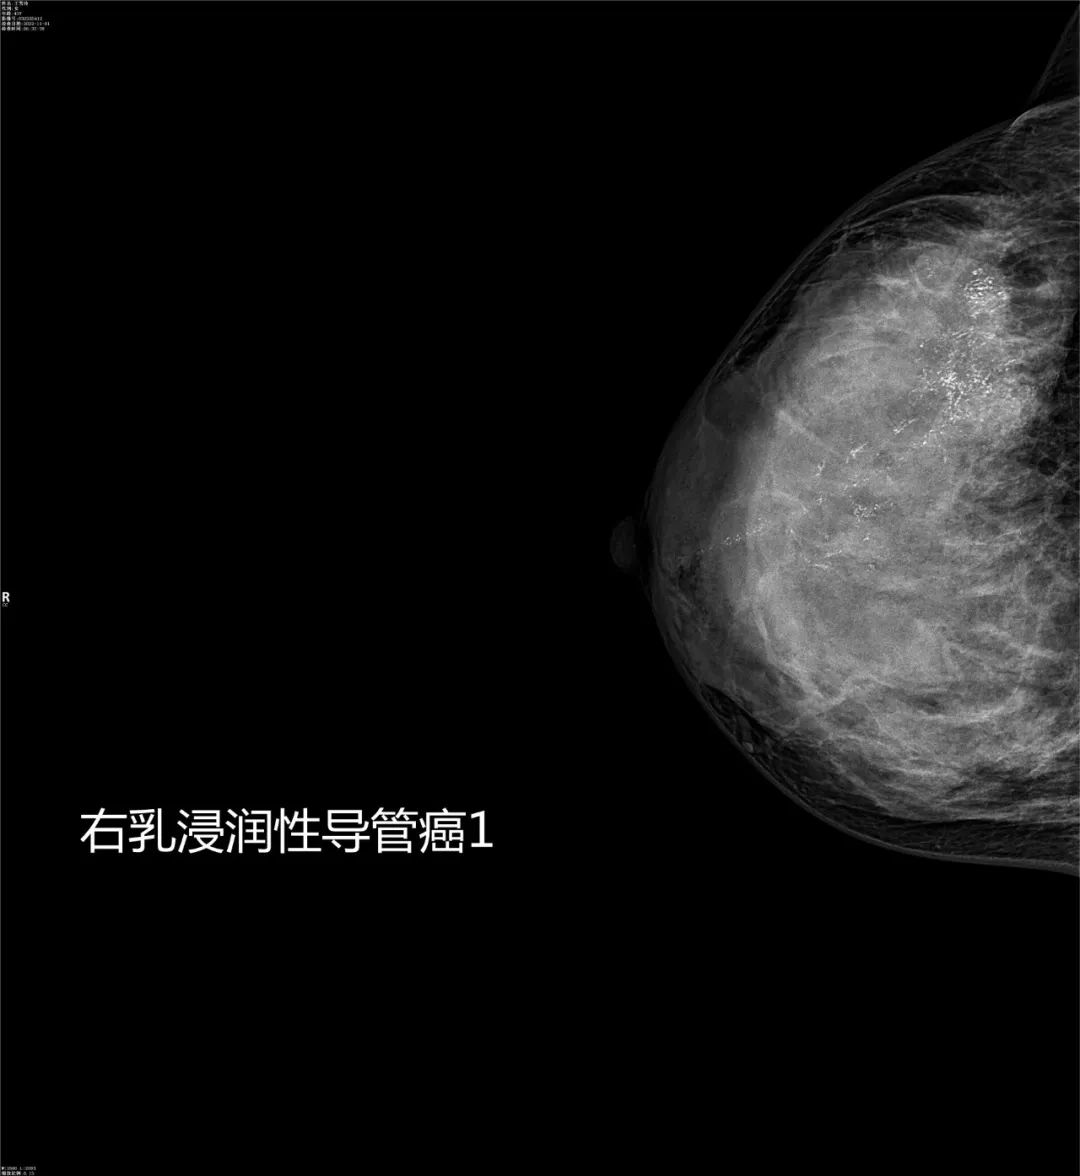

乳腺疾病的诊断与体检筛查